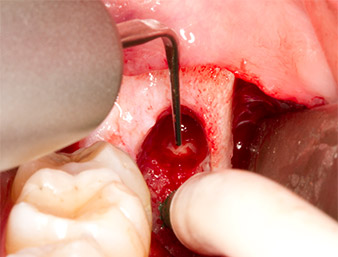

Nach Leitungs- und Lokalanästhesie wurde das Operationsfeld für einen bukkal-retromolaren Zugang weichgewebig eröffnet und dargestellt (Abb. 3).

sulkuläre Schnitt

Abb. 3: Der sulkuläre Schnitt beginnt Mitte des Zahnes 36, mit distaler Verlängerung am aufsteigenden Ast.

Das Gewebe über dem Wurzelrest war nicht vollständig verknöchert und bestand zu einem großen Teil aus entzündlich verändertem Granulationsgewebe (Abb. 4).